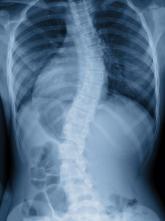

USPSTF goes neutral on adolescent scoliosis screening

Studies since 2004 suggest that the USPSTF “no longer has moderate certainty that the harms of treatment outweigh the benefits.”